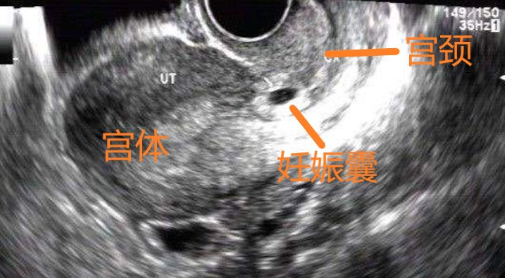

明確妊娠部位非常重要,應避免忽略性宮頸妊娠,行人流術導致陰道大出血危及生命安全。

宮頸妊娠的表現有

1.有停經史及早孕反應(血HCG增高)

2.一般在孕6周—8周時出現無痛性不規則陰道流血

3.出血量及出血時間不等,有時無任何誘因突然出現致命性大出血

4.查體時可有宮頸膨大、紫藍色著色